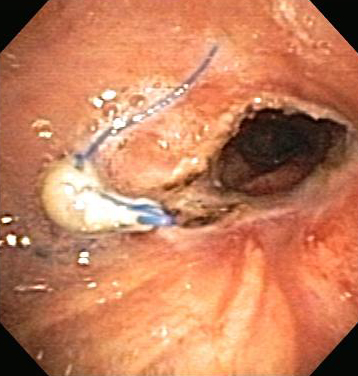

Бронхоскопическая терапия для обструкции нижних дыхательных путей правого главного бронха: постмеханическая циторедукция

Из коллекций Хосе Фернандо Сантакруза, дипломированного врача, члена Американской коллегии специалистов в области торакальной медицины, DAABIP, и Эрика Фолка, дипломированного врача, магистра наук; используется с разрешения